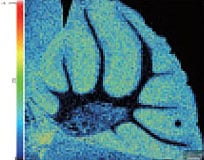

Applications are being studied using an analysis platform and images from an optical microscope and MS imaging system.

Imaging Mass Microscope